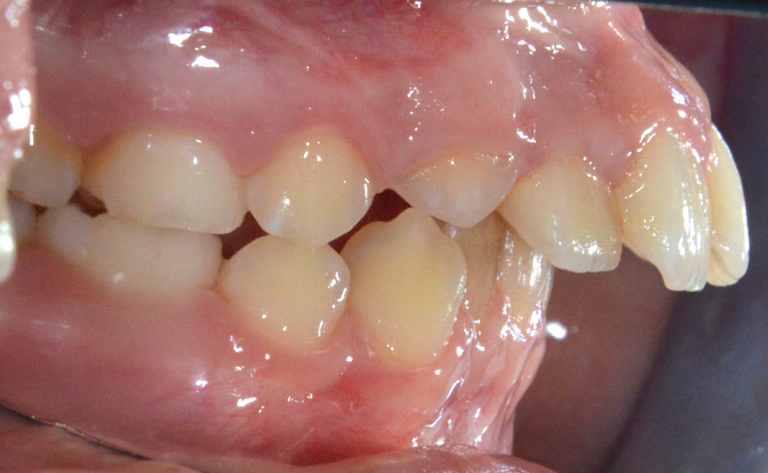

Die Lippen schützen die Zähne bei einem Sturz, Schlag oder einem Unfall. Stellen Sie sich mal vor, bei Ihrem Kind stehen die Frontzähne stark hervor, das heißt Ihr Kind hat eine große Frontzahnstufe (hier 10mm – normal sind 2-3mm). Es ist dann gar nicht möglich, ohne Mühe die Lippen zu schließen. Die Lippen sind dann meistens geöffnet, die Zähne schauen aus dem Mund heraus. Ein Sturz kann fatale Folgen haben.

Offene Mundhaltung mit vergrößerter Frontzahnstufe erhöht die Verletzungsgefahr für die Schneidezähne im Oberkiefer

Damit der körpereigene Airbag seine Funktion erfüllen kann, ist der mühelose und dadurch häufige Lippenschluss essenziell. Die Lippen üben bei einem kompetenten Lippenschluss Druck auf die Frontzähne aus und sorgen dafür, dass diese in einer physiologischen Position stehen. Fehlt dieser Druck durch beispielweise eine offene Mundhaltung, kann eine große Frontzahnstufe entstehen.